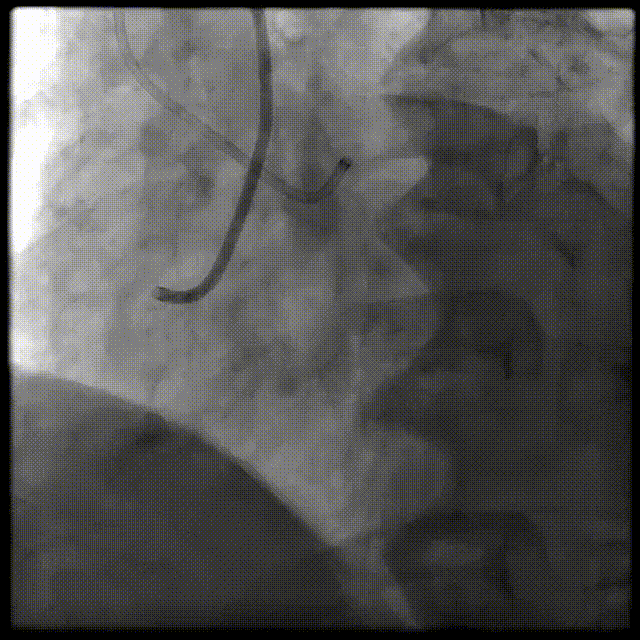

LCX远端100%闭塞;右冠低位开口且近端上翘走行,中远端闭塞。